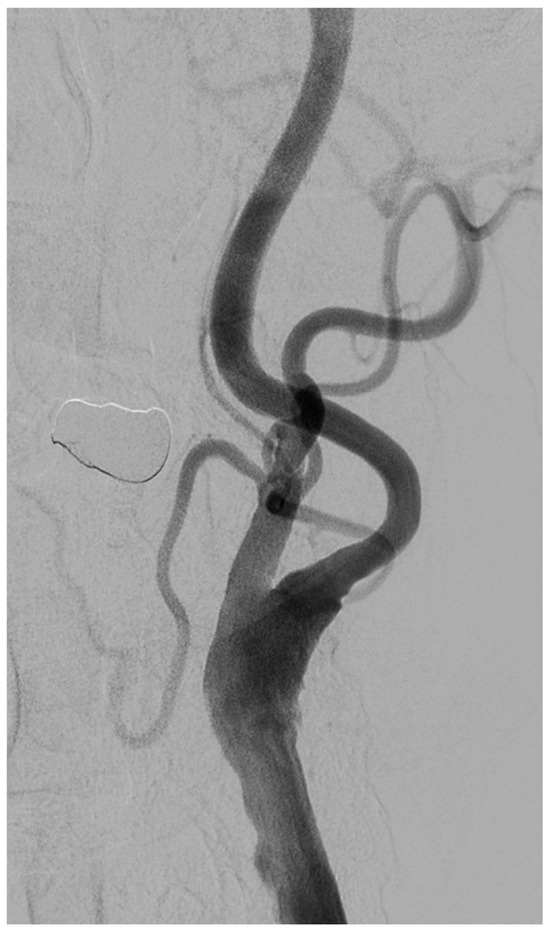

Carotid Stump Syndrome: A Case That Highlights the Necessity of Digital Subtraction Angiography for the Prompt Management of the Syndrome

Background and Clinical Significance: Carotid stump syndrome (CSS) is a rare and unexpected cause of recurrent ischemic ipsilateral events in the carotid vascular territory despite the demonstrated occlusion of the internal carotid artery (ICA). It is believed to be caused by microemboli due to turbulent blood flow in the patent stump of the occluded ICA that passes through anastomotic channels and retrograde flow into the middle cerebral artery circulation. Case Presentation: We describe the case of a 65-year-old male patient who suffered multiple concurrent transient ischemic attacks (TIAs) with a totally occluded ipsilateral ICA revealed by computed tomography angiography (CTA). He was diagnosed with CSS, which required the safest therapeutic approach. A further investigation with digital subtraction angiography (DSA) was performed, and a trickle of blood flow was observed in the reportedly occluded ICA. The diagnosis of a true ICA occlusion was withdrawn, and a diagnosis of pseudo-occlusion was established, affecting the final treatment strategy. Therefore, the patient underwent an ipsilateral carotid endarterectomy (CEA), and he has remained asymptomatic since then. Conclusions: The differentiation between a pseudo-occlusion and a true ICA occlusion is essential in promptly managing acute recurrent ipsilateral ischemic strokes in the carotid vascular territory. A further investigation with DSA in cases with a totally occluded ICA using CTA is essential for excluding pseudo-occlusions in ipsilaterally symptomatic patients. Full article